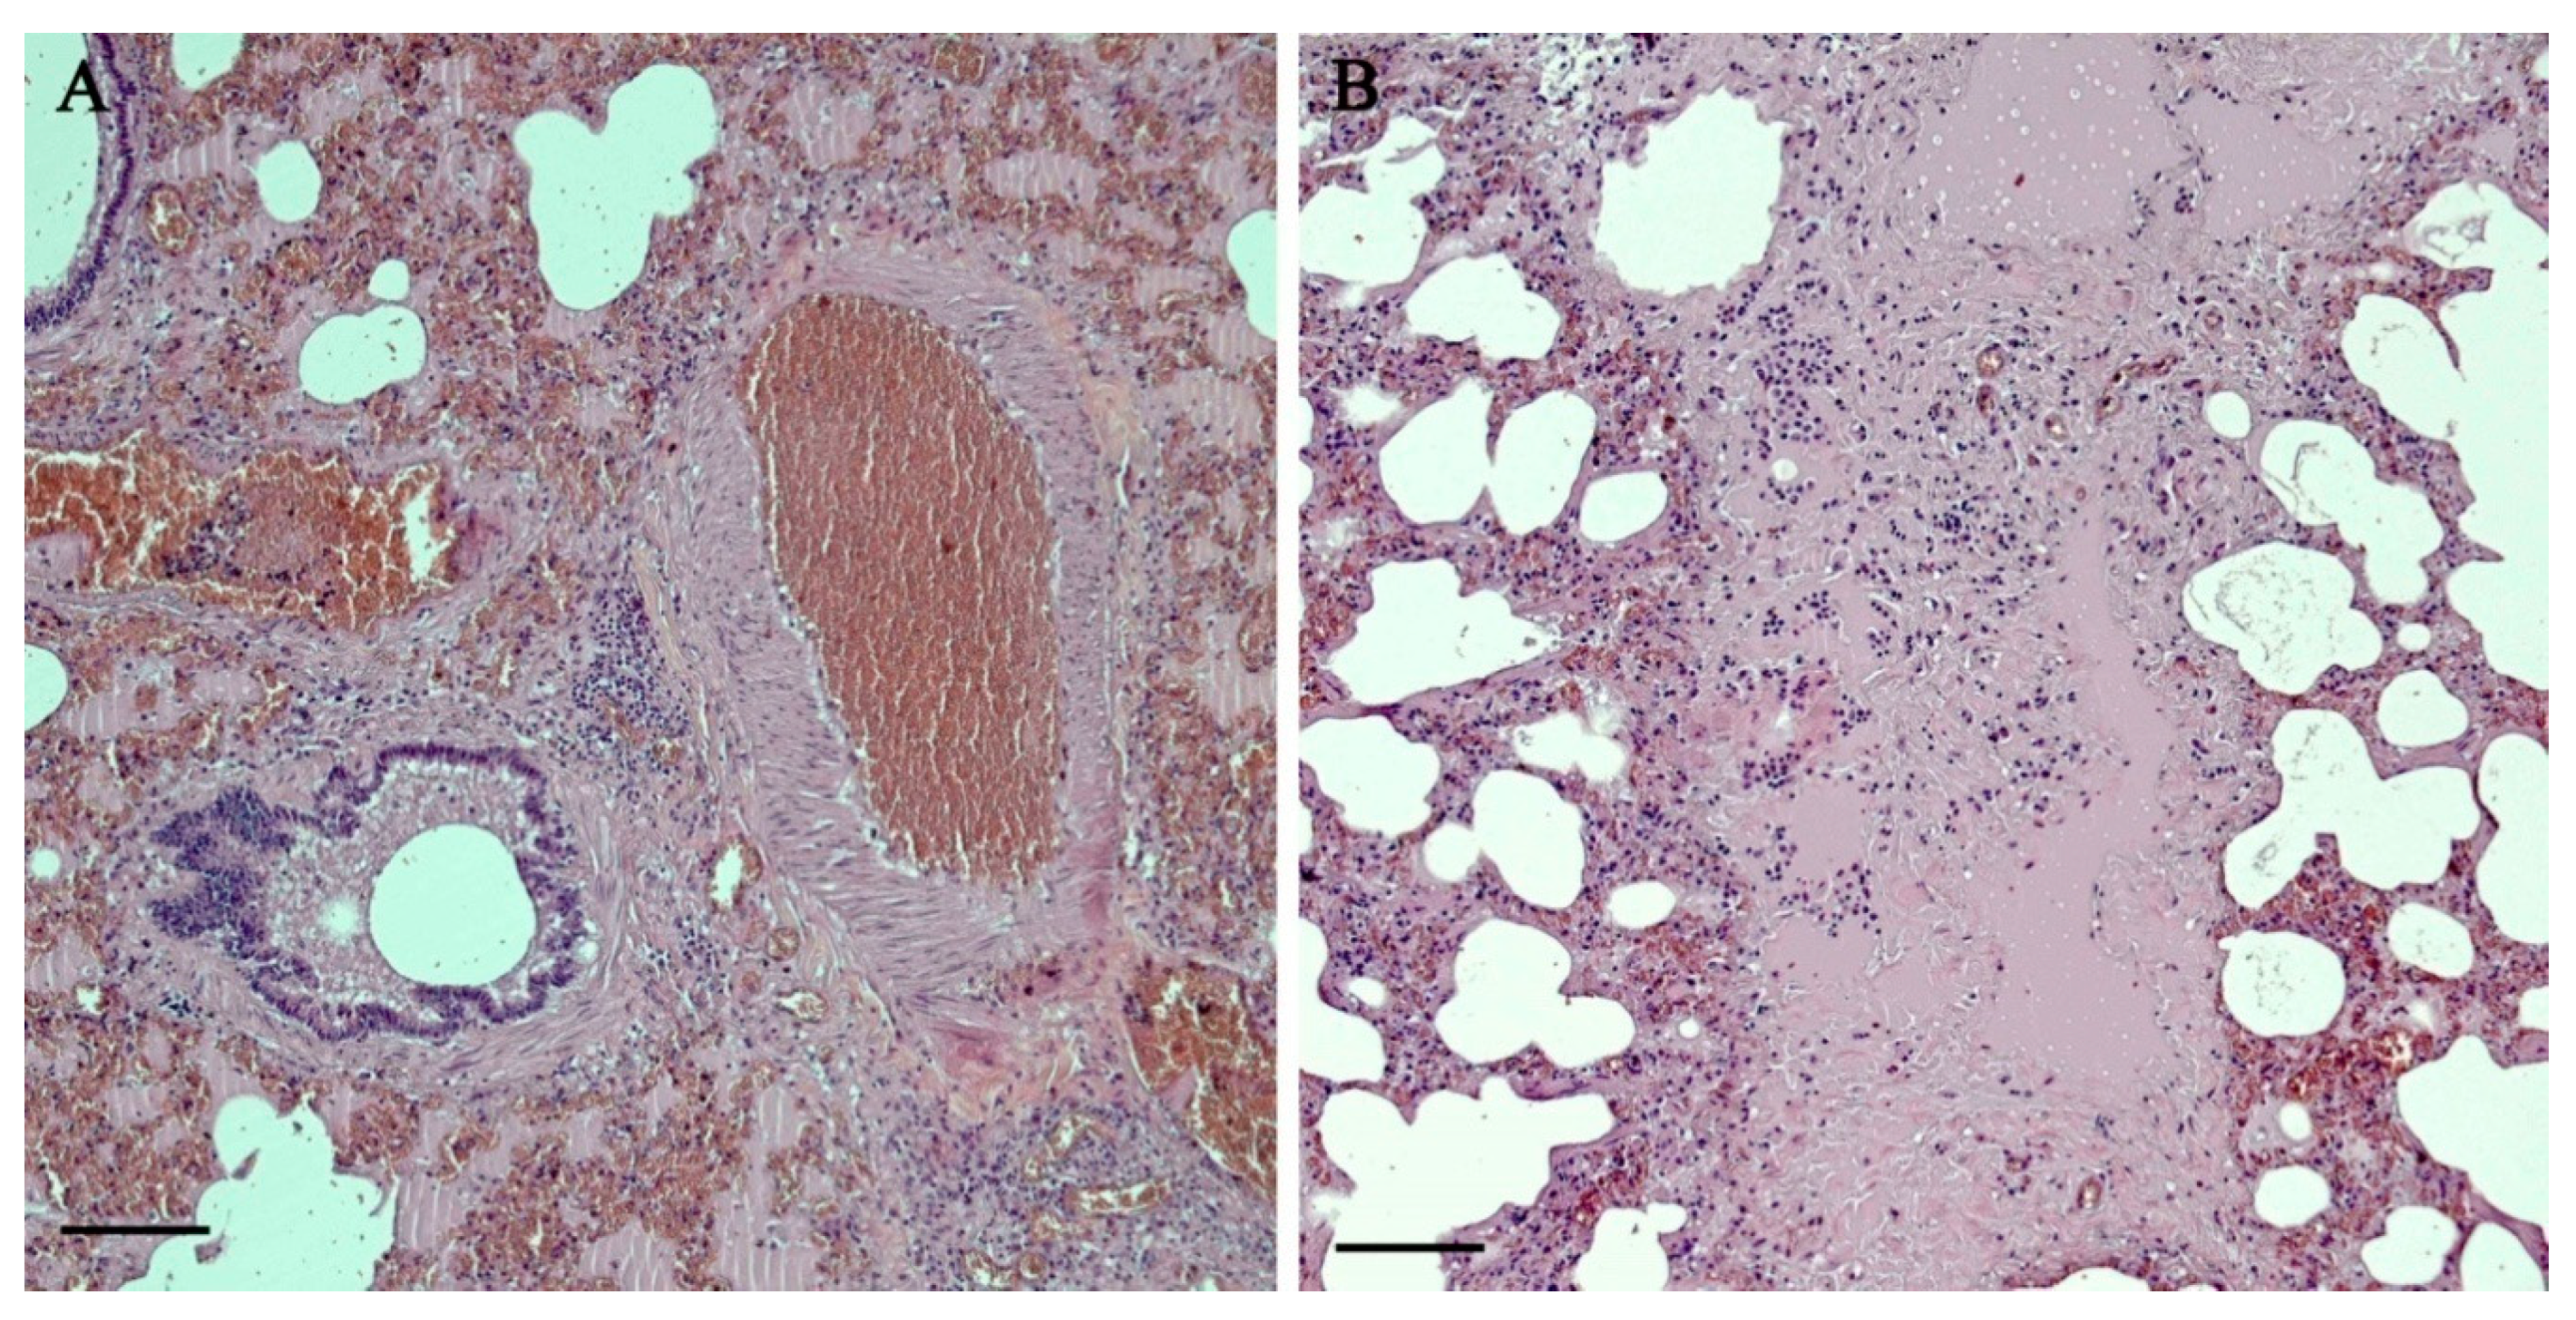

3.2. Histopathology